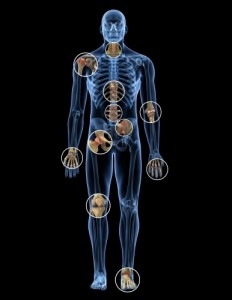

The 5 Types of Psoriatic Arthritis

Up to 30% of people with psoriasis will develop psoriatic arthritis, an autoimmune disease that can lead to pain, swelling, and stiffness in the joints. Psoriatic arthritis is generally divided into five subtypes, depending on which joints are affected and how many. But the system isn’t perfect. For instance, the five types don't take into accountsymptoms such as dactylitis (when the fingers and toes swell into sausages) and enthesitis(inflammation of areas near the tendons and ligaments).

Psoriatic arthritis Symptoms

Psoriatic arthritis is a chronic condition in which the immune system attacks the body, causing joint pain and other symptoms. It tends to develop in people with psoriasis.

"The most important thing for these patients is early recognition, diagnosis, and treatment of the disease," says Elaine Husni, MD, vice chair of the Department of Rheumatic and Immunologic Diseases at the Cleveland Clinic.

Many symptoms mimic other conditions or arthritis types, so psoriatic arthritis can be missed or misdiagnosed.

Shoulder Arthritis

One of the more common shoulder conditions Midwest Orthopaedics at Rush (MOR) physicians treat is pain from arthritis of the shoulders. Shoulder arthritis is not as prevalent as hip and knee arthritis, but it is relatively common. It typically affects patients over 50.